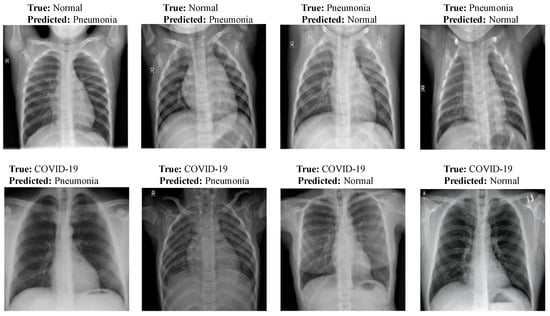

3.3. Misclassification Results Analysis

Figure 13 shows few misclassification results yielded by LW-CORONet on Dataset-1. These errors possibly occurred because of the similar visual features among the CXR images of the three classes.

Figure 13.

Sample misclassification outcomes of LW-CORONet.